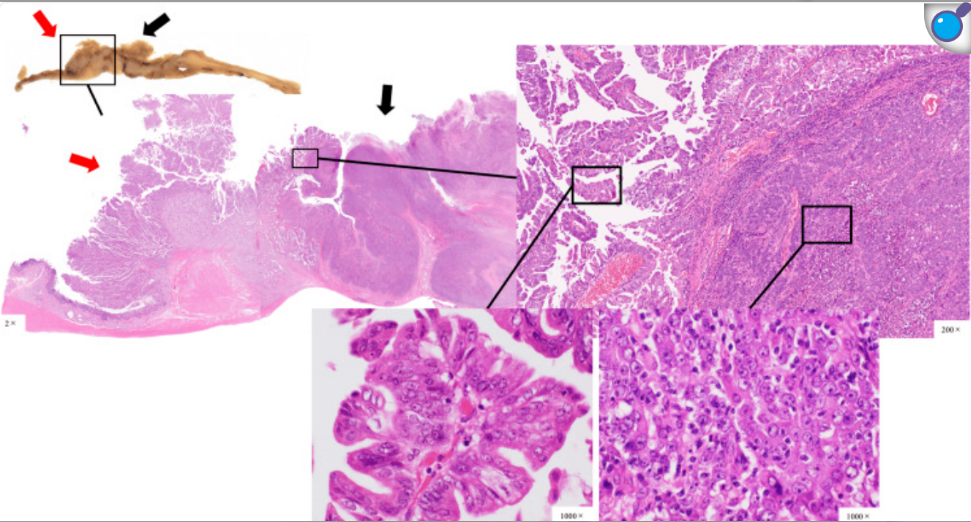

图2. 增强CT描显示胃窦壁增厚(红色圆圈)和幽门环附近淋巴结明显肿大(红色箭头) 患者接受开腹远端胃切除术、D2淋巴结清扫及Roux-en-Y重建。手术时间233分钟,失血48 ml,术后无并发症,第8天出院。 肉眼检查发现,Ⅲ型肿瘤位于胃前臂区,Ⅰ型肿瘤位于幽门环至十二指肠球部,两肿瘤在幽门环处交汇,与术前内镜结果不同(图3)。组织病理学检查显示Ⅲ型肿瘤以低分化腺癌为主,Ⅰ型肿瘤以中分化腺癌为主,边界清晰(图4)。

图3. 肉眼可见Ⅲ型肿瘤位于胃前壁区(黑色箭头),Ⅰ型肿瘤位于幽门环至十二指肠球部(红色箭头)。图像右侧为近端,左侧为远端。字母表中的字母分别对应各切面及其横切面。

图4. 组织病理学表现示Ⅲ型肿瘤(黑色箭头)主要由低分化腺癌组成,Ⅰ1型肿瘤(红色箭头)主要由中分化腺癌组成,两种肿瘤边界清晰 Ⅰ型肿瘤因位于幽门环十二指肠侧及Brunner腺区域被诊断为十二指肠癌。最终诊断为胃癌(50 mm×50 mm实性低分化腺癌为主)与十二指肠癌(31 mm×52 mm乳头状腺癌为主)的碰撞瘤。幽门下淋巴结转移中,1枚来自胃癌,1枚来自十二指肠癌。 免疫组化显示两癌均呈MUC5AC阳性,仅十二指肠癌呈MUC6阳性,CD10和MUC2阴性(图5)。因此,符合胃型十二指肠癌特征。